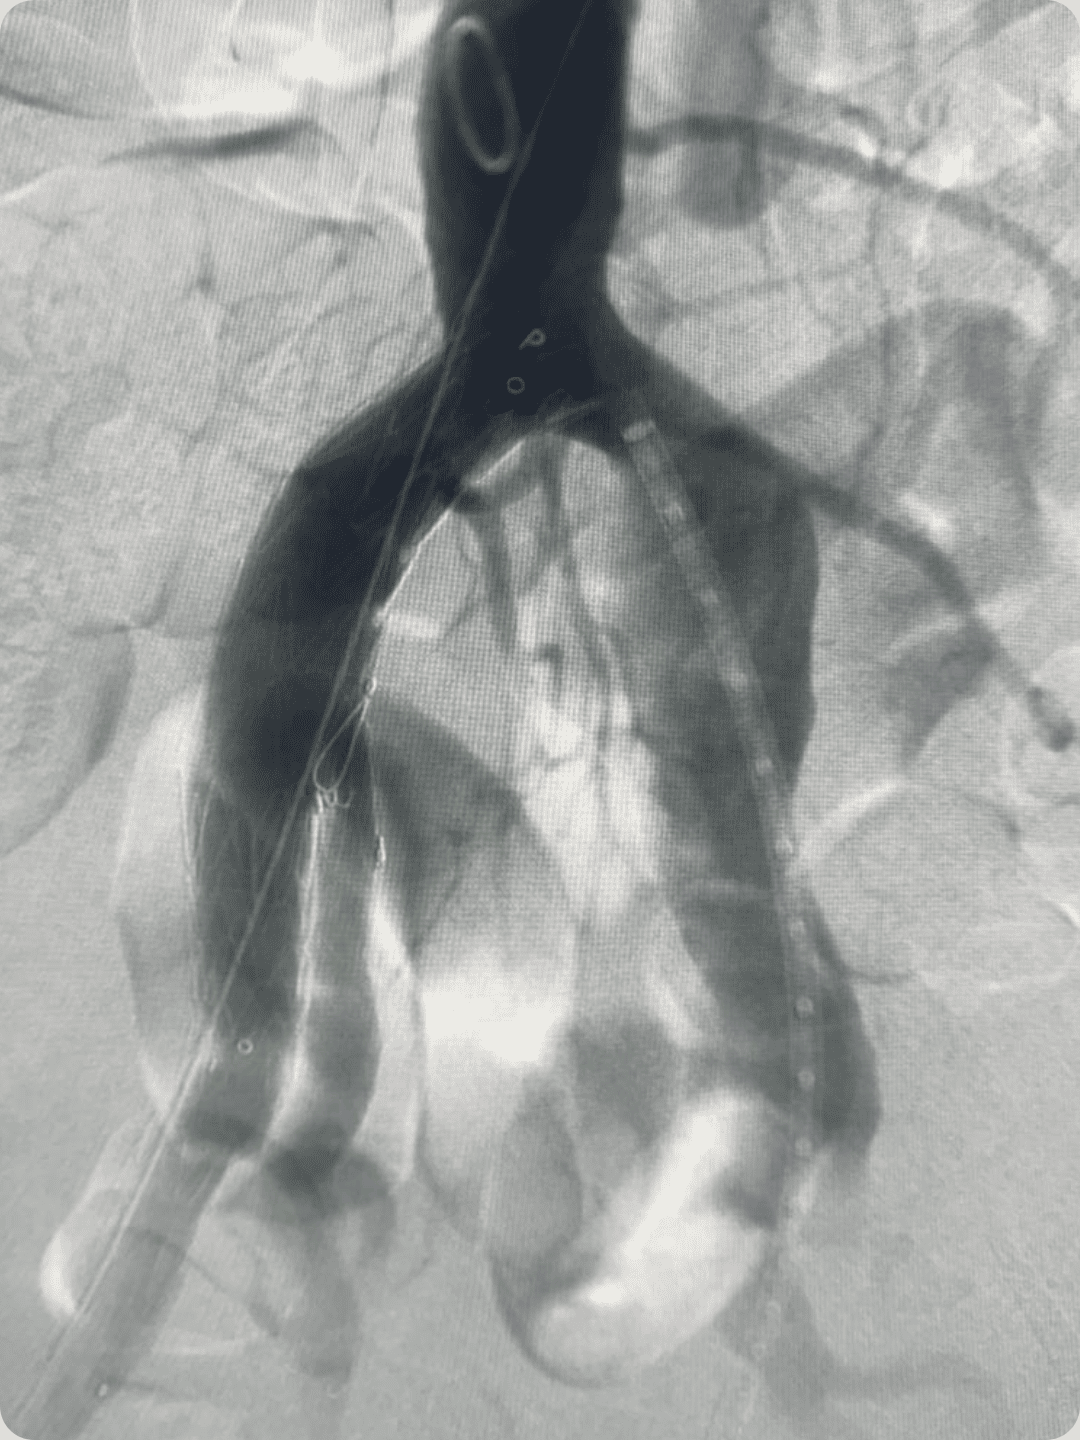

Resultado do clínico